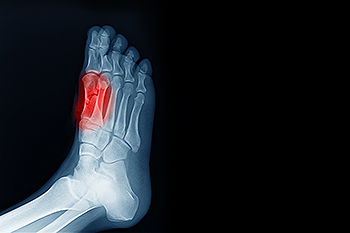

A dislocated toe occurs when the bones in a toe joint are forced out of alignment, often from a sudden impact, twist, or fall. This injury is common in sports and activities that involve jumping or quick direction changes. Symptoms include sharp pain, swelling, bruising, difficulty moving the toe, or a visible deformity. In some cases, a dislocation can occur along with a fracture. A podiatrist will examine the toe and confirm the injury with an X-ray to assess the position of the bones and check for any breaks. If the bones are out of place, a podiatrist may perform a closed reduction, a process that involves gently guiding the bones back into position. If the injury is more severe, surgery may be needed to restore joint alignment. Stabilization methods, such as splints or supportive footwear, may be used during recovery. If you are experiencing toe pain due to an injury or possible dislocation, it is suggested that you schedule an appointment with a podiatrist for an exam and appropriate treatment options.

In many cases the cause of toe pain is obvious, but in others, a podiatrist may want to use more advanced methods to determine the problem. These can range from simple visual inspections and sensation tests to X-rays and MRI scans. Prior medical history, family medical history, and any recent physical traumatic events will all be taken into consideration for a proper diagnosis.